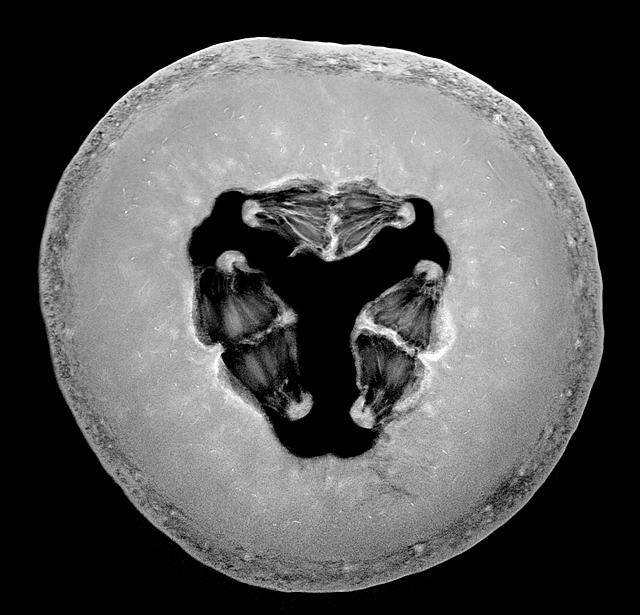

p3 S$ h* a6 T2 b9 r8 x石榴。图片来源:Andy Ellison

0 a, H7 }9 Q$ h下面是埃里森制作的GIF图,从上往下依次是杨桃、草莓和抱子甘蓝(左边彩图来自Shutterstock.com),最后是一张洋葱的3D图。% i! I: g6 d. x6 S: m- o9 o